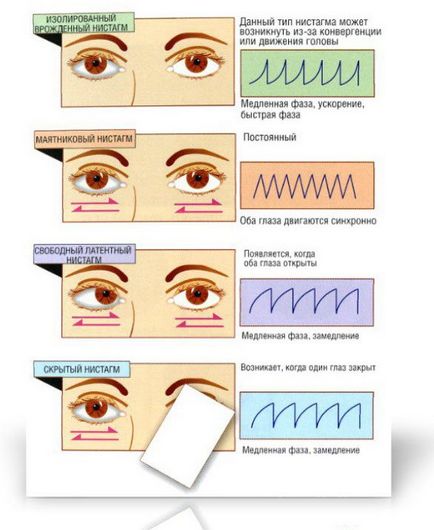

Minden megkülönböztetni a természet a mozgás Háromféle nystagmus:

- tolchkoobrazny - beleértve lassított és gyors defoveiruyuschie refoveiruyuschie korrekciós mozgás. Rezgések is eltérnek egymástól sebesség;

- hullámos, vagy mayatnikopodobny - azonos nagyságú lengések

- A vegyes típusú - magában foglalja a funkciók, mint egy szaggatott, és mayatnikopobodnogo nystagmus;

Attól függően, hogy a mozgás irányát kiadás:

- függőleges;

- forgás;

- átlós;

- vízszintes.

A látens nystagmus - előfordulása oszcillációk zárt vagy félig zárt szemek. Általában miatti fáradtság és megnövekedett nyomás a szemben.

Telepítés nystagmus - kis szaggatott rezgések maximális elrablását tanuló oldalon.